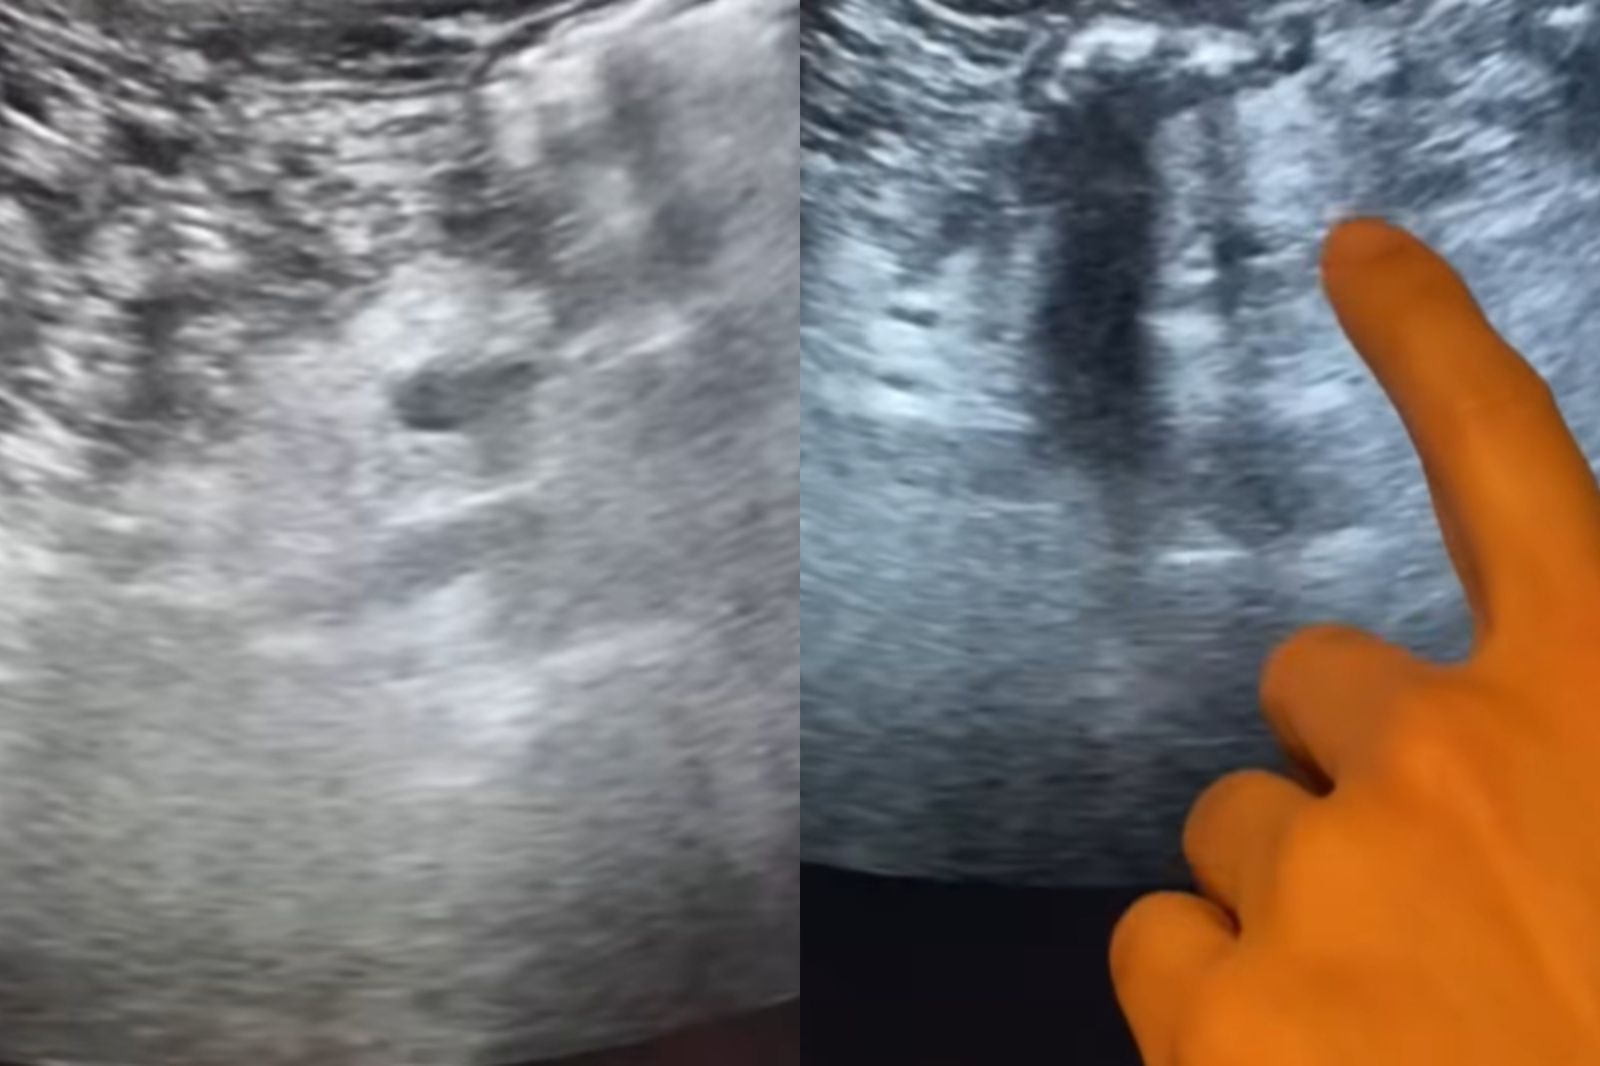

19日醫師錢政弘在臉書粉專「錢政弘 胃腸肝膽科醫師」中發布貼文,指出流行病學的調查顯示有「脂肪胰」的人會多6倍的胰臟癌風險,而有一半的胰臟癌病患發現有脂肪胰。顧名思義,脂肪胰就是有過多的脂肪堆積在胰臟中,在超音波下,胰臟實質回音會變得比肝臟或腎臟更亮(高回音),看起來顏色比較白。